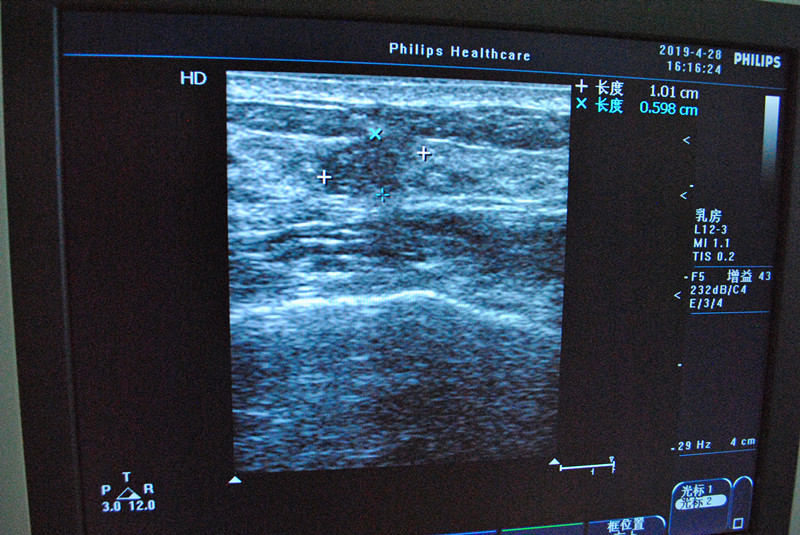

我院成功开展乳腺微创旋切手术

4月28日下午,我院外二科成功开展了3例乳腺微创旋切手术。